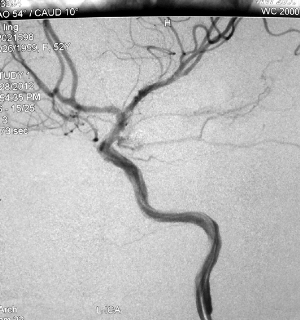

山东大学齐鲁医院神经外科杨扬教授是我国较早开展神经介入放射技术的青年神经病临床医学专家。他专门从事我国神经医学的发展、学术研究和国际学术交流工作,把全部精力都投入到神经介入医学的临床教育事业中;他努力跟踪国外先进技术,善于将临床试验与科学研究相结合,在脑与脊髓血管病发病机制、神经解剖基础研究、血液动力学、疾病分类以及栓塞材料的研制和改进等方面取得了丰硕的成果。在他和同行的共同努力下,我国神经病学科成就引起了国内外医学界的广泛重视,其中多项成果被国际医学界推广应用;他在学术研究方面成果突出,还应邀到国际会议上讲学……8+6\', 百拇医药

杨扬教授:我们学科的传统强项是脑血管搭桥显微血管吻合技术,并为后来在山东省率先开展颅内外低流量搭桥治疗烟雾病,及高流量搭桥手术治疗颅内复杂动脉瘤手术奠定了基础;更重要的是,当初刻苦练就的显微血管缝合技术也为今天的颅内复杂动脉瘤夹闭—血管搭桥—神经介入全方位协同治疗模式奠定了基础。这也确是“始料不及”的意外惊喜吧。1n, http://www.100md.com

杨扬教授:有世界公认最凶险的颅内动脉瘤―基底分叉动脉瘤夹闭手术,将我们学科中断了20多年的脑血管搭桥技术加以继承;还开展了颅内外低流量搭桥治疗烟雾病,及高流量搭桥手术治疗颅内复杂动脉瘤手术;经小脑延髓裂入路手术;枕下远外侧经髁入路手术;乙状窦前入路岩骨部分切除―回植手术。1n, http://www.100md.com

神经外科的手术经验和技巧都是实践中磨练出来的。杨扬教授从事“神外”临床已经25年,长期的手术经验技术积累使他对各种脑科手术游刃有余,不仅熟练掌握各种颅内外科疑难杂症的治疗,更是对脑血管搭桥术、颅内动脉瘤开颅夹闭及介入神经外科手术有着十分丰富的临床经验。$u, 百拇医药

杨扬教授为临床技能型医师,专业特长:1.脑血管外科。擅长脑血管显微外科技术:包括颅内动脉瘤、脑血管搭桥、动静脉畸形、颈动脉内膜剥脱等手术及神经介入治疗技术。2.颅底外科(脑膜瘤、垂体腺瘤、颅咽管瘤、听神经瘤等)手术。杨扬教授在国际神经病学权威杂志发表SCI收录论文3篇,内容均为临床实用技术。$u, 百拇医药

杨扬教授继承并不断完善齐鲁医院神经外科的传统强项——脑血管搭桥显微血管吻合技术,为后来在山东省率先开展颅内外低流量搭桥治疗烟雾病及高流量搭桥手术治疗颅内复杂动脉瘤手术奠定了基础。他为神经介入做技能培训,为颅内复杂动脉瘤夹闭—血管搭桥—神经介入全方位协同治疗模式奠定基础。杨扬教授先后在数十个人体解剖头颅标本上进行过神经外科局部解剖手术模拟练习,为临床上完善颅底外科手术技术奠定了基础。他参加了2008年卫生部认证的内镜规范化培训,获得全国神经内镜使用资格证书,并在临床上开展了神经内镜辅助微创手术。$u, 百拇医药

杨扬教授在国内外有影响力的临床特色技术有:1.硬膜外前床突切除视神经减压手术方式:有关论文已在神经病学科国际高级别刊物《Neurosurgery》上发表,这标志着山东齐鲁医院神经外科在国内外颅底外科领域拥有了无可争议的地位;2.神经导航系统下辅助三叉神经射频卵圆孔穿刺技术:相关论文已经发表在国际影响力的杂志《The Clinical Journal of Pain》上,并引起了世界知名专家的关注;3.纵裂入路胼胝体开窗技术:杨扬教授在临床上的治疗思路受到国际知名专家的认可,这种完全独立开发的全新手术方式,在我国神经外科史上可谓独创。论文已在国际神经外科知名杂志《World Neurosurgery》上发表。4.线锯穿过眶下裂的额颞眶颧开颅技术:克服了传统额颞眶颧开颅中眶下裂难以定位的问题,明显简化了手术步骤。论文发表在国内神经病学科非常具影响力的《中华神经外科杂志》上。$u, 百拇医药

有人戏称神经外科医生是“和神并驾齐驱的医生”。杨扬这个“神外”医生拥有25年从业经历,这使他对各种脑科手术游刃有余。手术经验和技巧都是实践出来的。长期的技术积累,让杨扬不仅熟练掌握各种颅内外科疑难杂症的治疗方法,更是积累了十分丰富的脑血管搭桥术、颅内动脉瘤开颅夹闭及介入神经外科手术经验。$u, 百拇医药

杨扬教授每年诊断治疗神经介入手术例数上百例,他继承并完善了齐鲁医院神经外科的传统强项——脑血管搭桥显微血管吻合技术,为后来在山东省内率先开展颅内外低流量搭桥治疗烟雾病,及高流量搭桥手术治疗颅内复杂动脉瘤手术奠定了基础。杨扬教授在山东省内率先开展了多项高难度、高风险手术,包括世界公认最凶险的颅内动脉瘤——基底分叉动脉瘤夹闭手术。他医风严谨,完全从临床实用知识理论和技能的研究出发,理论联系实际,建立了显微神经外科局部解剖及手术技能培训实验室,推出多项临床新技术,在专业领域里不断做出新贡献。$u, 百拇医药